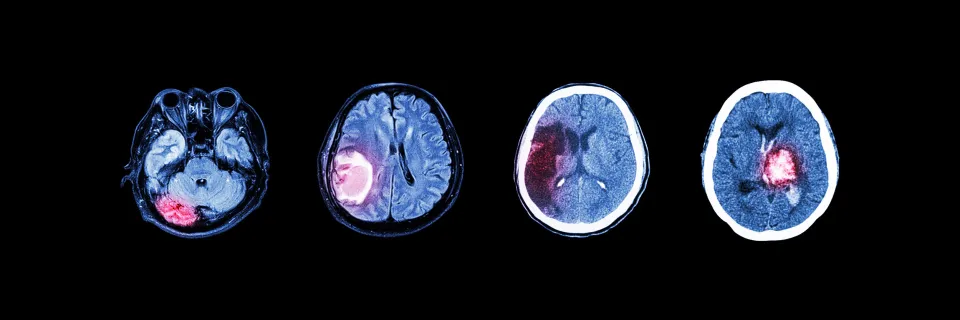

Il existe de très nombreuses maladies tumorales du système nerveux central qui se développent à partir des cellules du cerveau et de la moelle épinière. Les symptômes et la gravité des tumeurs cérébrales et du système nerveux central varient selon leur nature, leur localisation, leur taille et leur grade.

Parmi elles, les gliomes se développent à partir des cellules gliales qui entourent les neurones. Ce groupe de tumeurs inclut les astrocytomes, les oligodendrogliomes, les épendymomes et les gliomes mixtes. Les gliomes peuvent être agressifs, dans ce cas on parle de haut degré de malignité, ou avoir un comportement plus indolent (bas grade). Les astrocytomes de plus haut grade sont connus sous le nom de glioblastome. Le pronostic dépend des anomalies et des mutations génétiques qui caractérisent les différents gliomes.

Les méningiomes se développent dans les cellules des méninges qui sont les enveloppes recouvrant le cerveau et la moelle épinière. Les lymphomes se développent le plus souvent dans les ganglions lymphatiques, mais peuvent aussi apparaître dans le cerveau.

Il existe encore les tumeurs de l’hypophyse, les neurinomes, les médulloblastomes et des dizaines de maladies tumorales rares.

A noter que l’on parle de métastases cérébrales lorsqu'un cancer apparaît dans une partie du corps et se propage au cerveau.